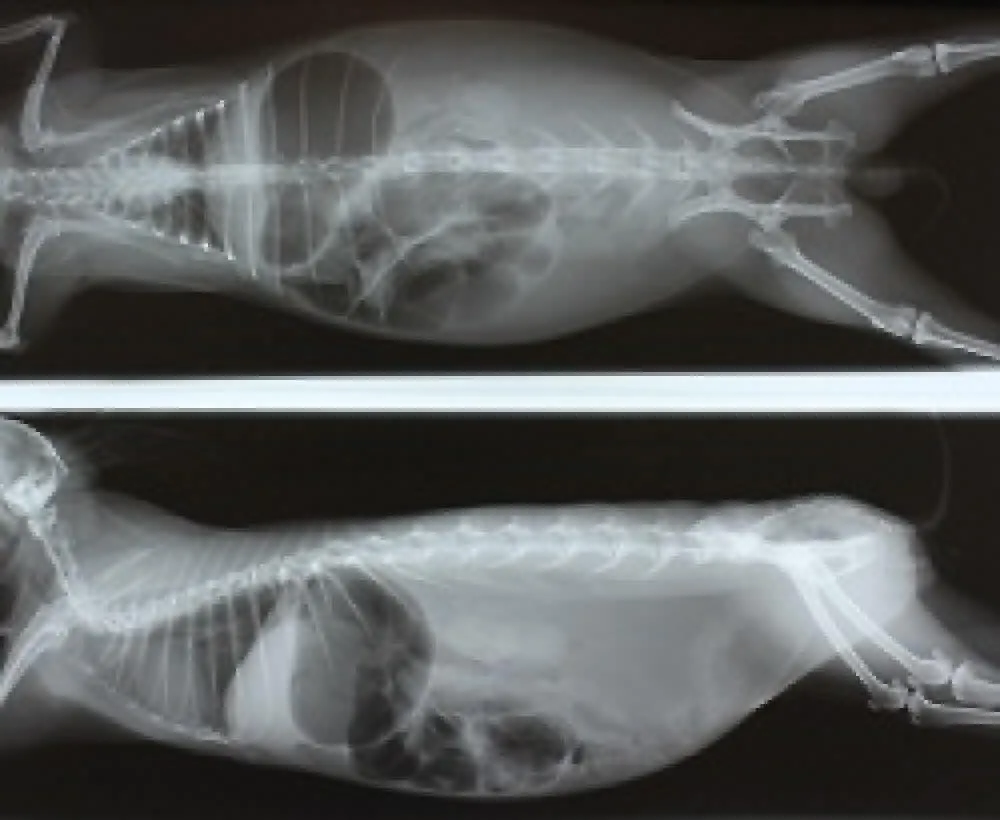

消化器の病気(胃腸のうっ滞)

●症状:食欲元気の低下、便が小さい、便が出ない、お腹が張っている

ウサギは身体の構造的に吐くことができません。何らかの原因で胃腸の動きが止まってしまうと、胃液やガスが胃腸内にたまり、腹痛を起こします。

多くの場合、内服や注射、補液などの内科的な治療で改善しますが、緊急の処置が必要になることもあります。

急性の胃拡張において、内科治療に反応しない時や重度の胃拡張では、経口胃カテーテルによる速やかな胃液の抜去が必要です。

原因の多くは不適切な食事による慢性的な繊維質不足です。草食動物であるウサギの胃腸が正常に機能するためには、繊維質を豊富に含む乾草が必要です。

他の病気に続発することも多いです。正しい食事バランスを心がけ、普段から糞の大きさや数などを観察しておき、糞が小さい、量が少ないなどの異常に気付いたら、すぐに受診をおすすめします。

![]() | ![]() |

| ■胃と盲腸のガス貯留 | ■胃拡張の手術 |